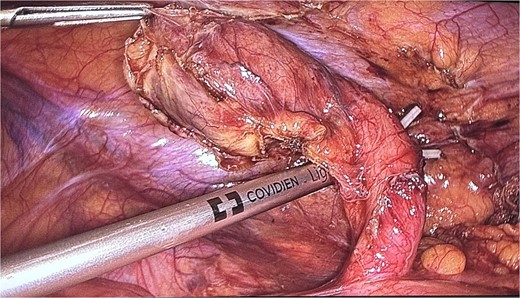

The patient was admitted and scheduled for a laparoscopic appendectomy. During surgery, the appendix was identified in the retrocecal position, extending to the right paracolic gutter. It was dissected from surrounding tissues, revealing a large mass at the tip and multiple nodules on its surface. The surgical team employed minimal manipulation techniques to avoid tumor rupture, suspecting a carcinoid or other appendicular tumor (Fig. 4). The mesoappendix was dissected and transected at the base using an EndoGI stapler. The specimen was removed in a bag and sent for histopathology (Fig. 5).

An intraoperative picture of an acutely inflamed appendix with mass seen at the tip; the mass was manipulated carefully and grasped at peri-appendicular tissue to avoid mass rupture.